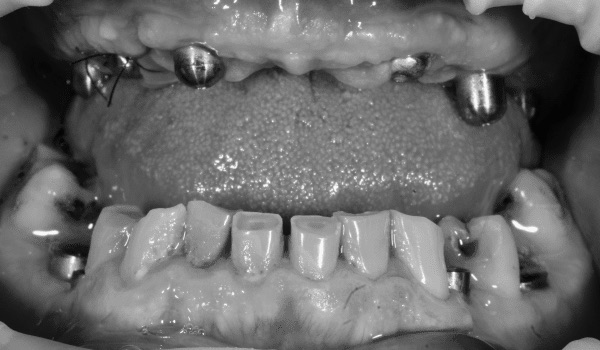

Истории лечения наших пациентов в формате "до-после"

Империя здоровых и красивых улыбок